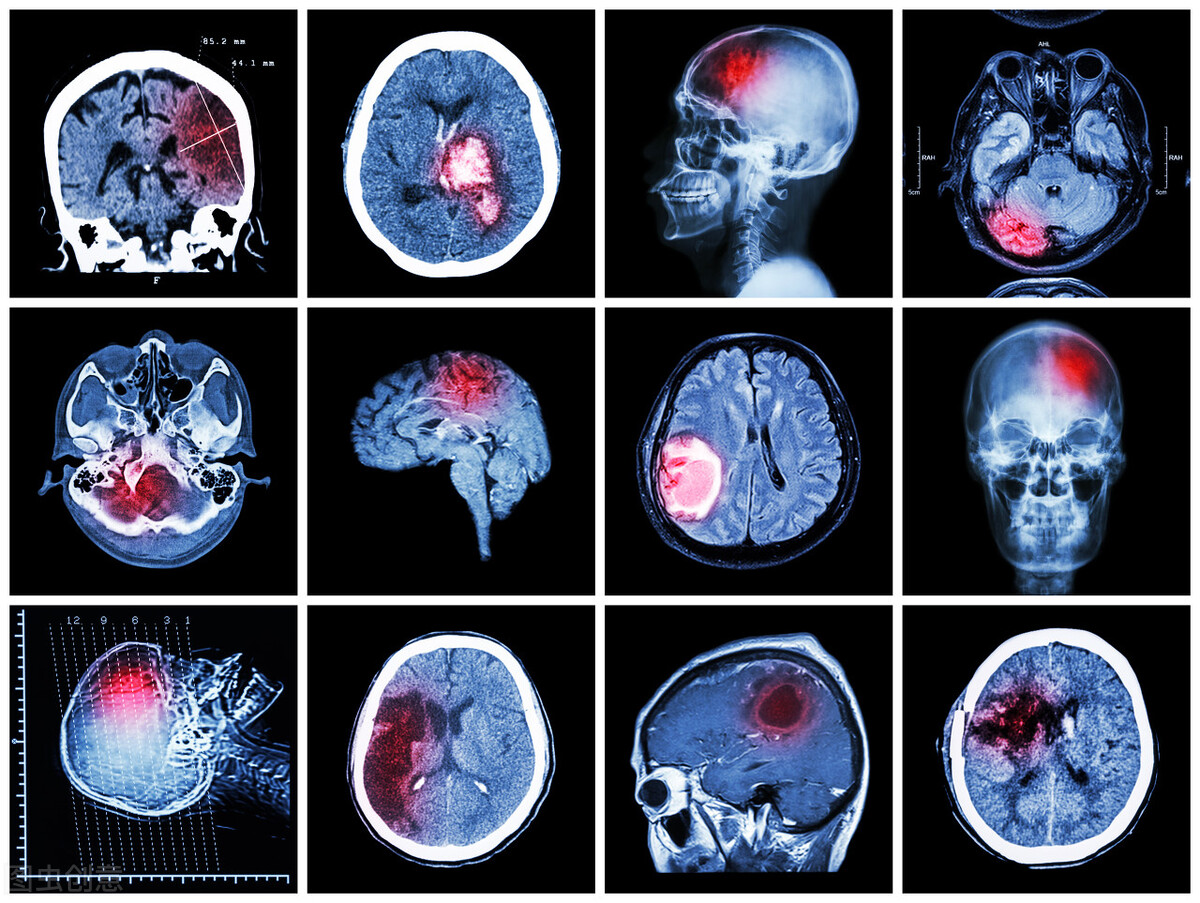

脑梗看似温和,实际上却非常可怕!

这种忽略是非常严重的,随着患者病情的快速恶化,一旦发生不良事件,就会达到和心梗同样危急的处境,需要立刻马上开展急救,毕竟细胞组织的不可再生性是相同的,一个抢救不及时,就可能导致死亡的来临,而且相比于心梗,脑梗患者除了死亡的结局以外,还有一种残疾的结局,他们虽然抢救得比较成功,保住了生命健康,但依然坏死了大量的细胞组织,因此会对各系统功能有所影响,这就叫做后遗症,恢复难度较高,而且对于部分人群而言,比死还要可怕。

而我们针对脑梗的治疗,第一步原因是探查诊断,找出导致脑梗最主要的致病源,然后对其进行针对性治疗,自然会令患者恢复,而近十几年间,脑梗低龄化趋势越发明显,现在别说三四十岁的患者,即使二十多岁的脑梗患者也不少见,对于他们而言,高龄导致的动脉硬化可能性实在太小了,如果还按照以前的应对办法,实在过于消极。另外还有一些特殊群体,比如我前天接诊的这位季先生,他们每天在寺庙里活动,并且清淡饮食,却依然早早患上脑梗。所以经过一系列检查,我发现他的颈部病变极为严重,后来跟他聊天,他也有所醒悟,说可能是天天研究经书、*坐静**诵经所致。

各位朋友,千万不要认为颈部和脑梗没有联系,在临床上很多脑梗患者都是颈部病变所致,这个比例还在逐年增长,颈部位置特殊,是心脏和大脑的唯一连接处,心脏供给大脑的血液都要从这经过,一旦颈部病变过于严重,就会令这个重要通道减小,影响大脑的供血量,使得其逐渐发生缺血,各大区域组织坏死,威胁生命健康。